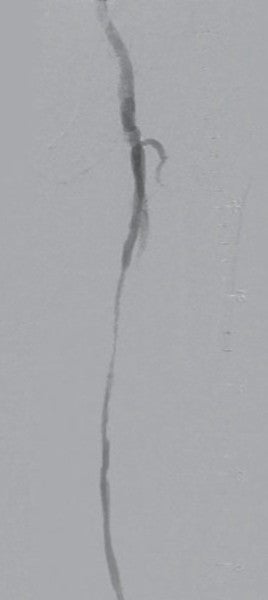

対側CFAより6 Fr 45 cm長のガイディングシースを挿入し山越えにて左EIA遠位部に進めた。この時点で圧波形は問題なかったため、手技を継続することとした。まず、5.5 Fr 100 cm長のガイディングカテーテルのバックアップ下、IVUSガイドに0.014 inchガイドワイヤー(先端荷重3 gポリマージャケットタイプ)を進めたところ、比較的容易にガイドワイヤー通過に成功した。IVUSでは全長にわたり intraplaqueを通過していたものの、血栓成分の多いプラークと考えられた。このため、5.5 FrのガイディングカテーテルをSFA遠位部に先進し、フィルターワイヤー(径 8 mm)を膝窩動脈に留置し遠位部保護を行った。続いて、5.5 Frガイディングカテーテルを用いて血栓吸引を行ったうえで、小径バルーン径 4.0 mm / 長 220 mmを使用し6 atmで前拡張した。(図3)この時点で造影にて末梢塞栓のないことを確認しフィルターワイヤーを回収、0.035 inchガイドワイヤーを用いて7 Fr 55 cm長のガイディングシースへ交換した。0.014 inchガイドワイヤー(先端荷重 1 g 親水性コートタイプ)を挿入後、SFA遠位よりバイアバーン® ステントグラフト径 7.0 mm / 長 150 mmを留置し、バルーン径 6.0 mm / 長 80 mmを用いてステントグラフト内のみ 18 atmで後拡張を行った。続いて、SFA近位部のlanding zoneをIVUSマーキングしたうえで、(図4)バイアバーン® ステントグラフト径 7.0 mm / 長 100 mmを追加留置した。先述のバルーン径 6.0 mm / 長 80 mmを用いて高圧拡張の後、近位部のみバルーン径 7.0 mm / 長 100 mmを使用し12 atmで後拡張を追加した。IVUSにてステントグラフトの拡張が良好かつmalpositionがないことを確認した。 最後に、EIAに対してベアメタルステント(BMS)径 10 mm / 長 60 mmを留置、後拡張を行って手技を終了した。(図5、6)

比較的血栓成分の多いSFAのCTO病変であり、遠位塞栓をいかに予防するかを考える必要があった。遠位塞栓の予防方法としては、フィルターデバイスの使用あるいは外部からの物理的圧迫が挙げられるが、今回は患者負担も考慮しフィルターデバイスを使用した。また、血栓吸引後の前拡張では小径バルーンを用いて、できるだけ低圧で行い、後拡張でもバイアバーン® ステントグラフト径より1 mmアンダーサイズのバルーンを使用した。また、近位端のみ同径サイズのバルーンを使用することすることにより、血栓成分を飛ばさないように配慮した。バイアバーン® ステントグラフトは理論的にはグラフト素材によるメカニカルバリア機能によって病変を押さえ込むことができると考えられるため、他デバイスに比し血栓が多く含まれる可能性のある病変でも適しているデバイスと考えられる。ほか、バイアバーン® ステントグラフトの位置決めについては、DFAならびに側副血行路を塞がないように正確に留置することが望ましいが、当院においては必ずIVUSマーキングを行って正確なデバイスの位置決めを心がけており、本症例でも正確な位置に留置することができた。本症例は、患者の職業上、運動量が多く治療前は業務に支障をきたしていたが、術後は完全に症状が消失し業務遂行が可能になったとのことであった。現在、 外来にて3年フォローが完了しているが、良好な経過を維持できている。